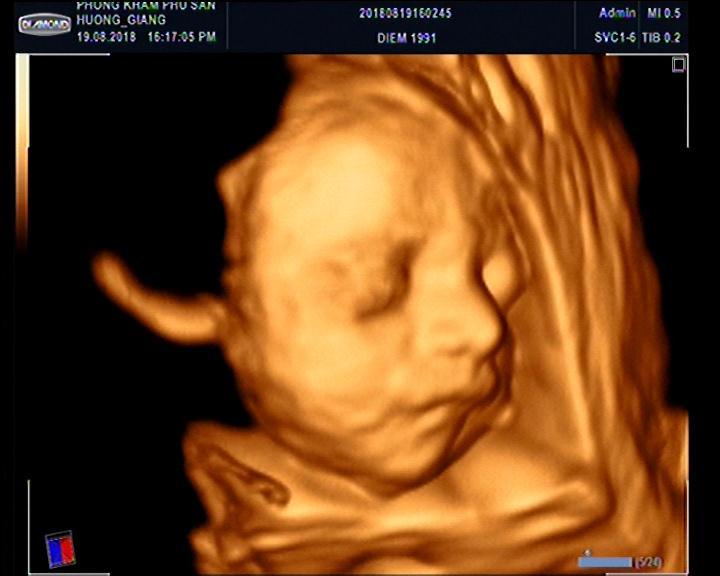

Tại Quảng Ngãi, Phòng khám Sản Phụ Khoa BS Vũ - BS Khuê là địa chỉ được nhiều bà bầu lựa chọn làm địa chỉ chăm sóc và theo dõi quá trình thai kỳ. BS Khuê được đánh giá là chuyên gia chuẩn đoán hình ảnh hàng đầu, thế mạnh là xác định dị tật thai nhi chính xác. Việc theo dõi sức khỏe của cả bé và mẹ trong suốt giai đoạn mang thai được tiến hành khá kỹ lưỡng. Phòng khám khá cởi mở với khách hàng, và phục vụ tận tình, giúp các mẹ bầu an tâm khi siêu âm và khám thai.Phòng khám Sản Phụ Khoa BS Vũ - BS Khuê khám thai, theo dõi thai kì, siêu âm thai 4D-5D, xét nghiệm NIPT, double test… Ngoài ra, mẹ bầu cần lưu ý một điều là phòng khám khá đông nên để không mất thời gian nên gọi điện để đặt lịch hẹn trước.

Gọi điệnBác sĩ Hà Tấn Ngọc hiện công tác tại khoa Phụ Sản bệnh viện Đa khoa Phúc Hưng, là một bác sĩ giỏi và tận tâm chuyên về lĩnh vực Sản khoa. Ngoài giờ hành chính, bác sĩ làm việc tại phòng khám, siêu âm thai 5D Hà Tấn Ngọc. Phòng khám có không gian khá rộng rãi, sạch sẽ, trang bị các trang thiết bị đảm bảo cho thăm khám thai sản. Hiện tại, với mong muốn mang lại cho mẹ và bé những điều tốt đẹp nhất từ trong gian đoạn thai nghén; mang lại những hình ảnh rõ nét, trung thực nhất, phòng khám đã trang bị dịch vụ siêu âm 5D.